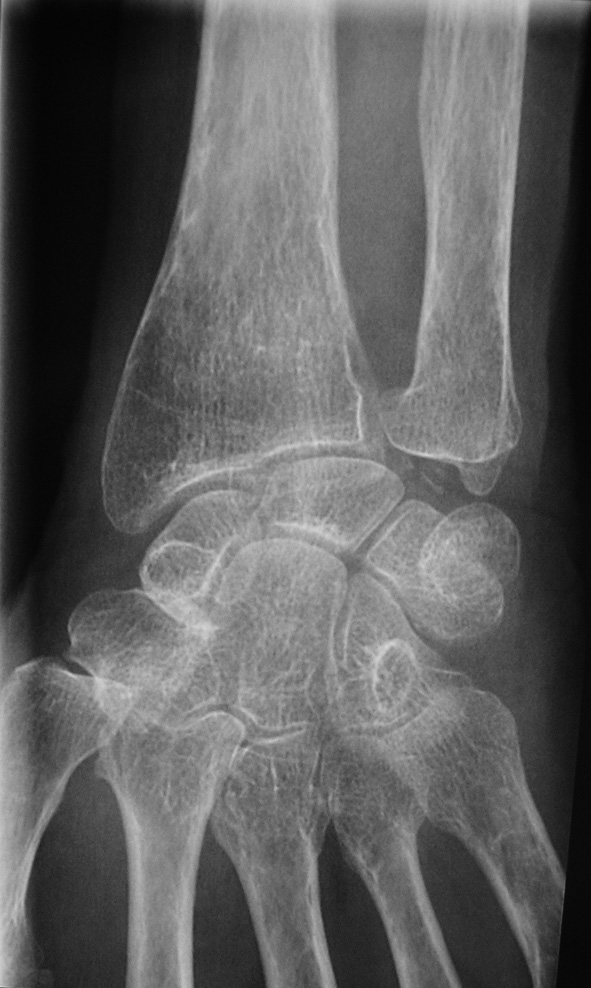

Dans ses antécédents, vous notez une arthrite du genou droit il y a un an — elle vous apporte une radiographie de cette époque —, une hypertension artérielle traitée par Nifédipine, une appendicectomie.